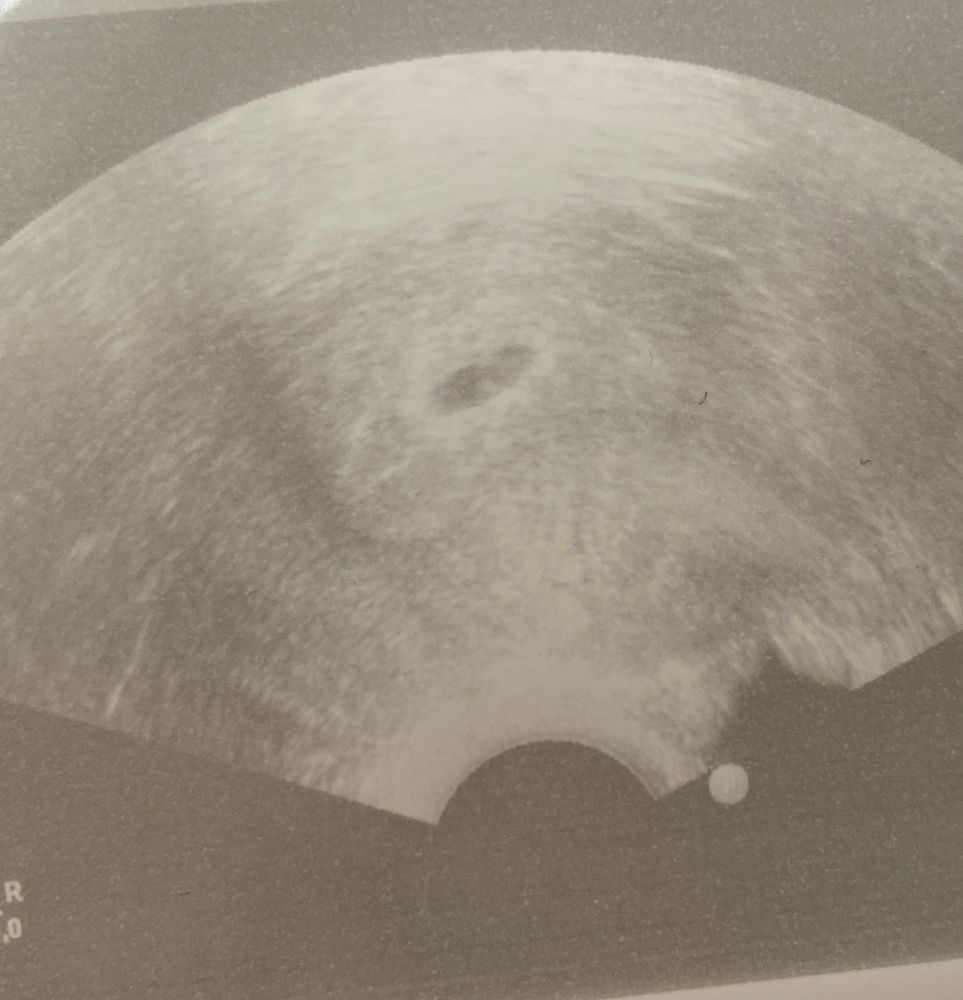

Первое узи ❤️

Удачи вам 🤞я тоже вчера была на узи, сердечко видела 🥰